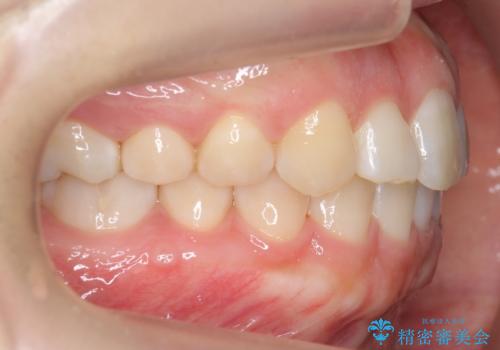

よくある悩み 前歯が裏に2本入っているのを治したい

- 前歯が2本裏に入ってしまっているのを治したいとのことでした。

最小限の抜歯により矯正ができたと、喜んでいただきました。